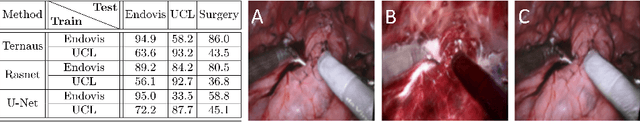

Abstract:Surgical instrument segmentation for robot-assisted surgery is needed for accurate instrument tracking and augmented reality overlays. Therefore, the topic has been the subject of a number of recent papers in the CAI community. Deep learning-based methods have shown state-of-the-art performance for surgical instrument segmentation, but their results depend on labelled data. However, labelled surgical data is of limited availability and is a bottleneck in surgical translation of these methods. In this paper, we demonstrate the limited generalizability of these methods on different datasets, including human robot-assisted surgeries. We then propose a novel joint generation and segmentation strategy to learn a segmentation model with better generalization capability to domains that have no labelled data. The method leverages the availability of labelled data in a different domain. The generator does the domain translation from the labelled domain to the unlabelled domain and simultaneously, the segmentation model learns using the generated data while regularizing the generative model. We compared our method with state-of-the-art methods and showed its generalizability on publicly available datasets and on our own recorded video frames from robot-assisted prostatectomies. Our method shows consistently high mean Dice scores on both labelled and unlabelled domains when data is available only for one of the domains. *M. Kalia and T. Aleef contributed equally to the manuscript